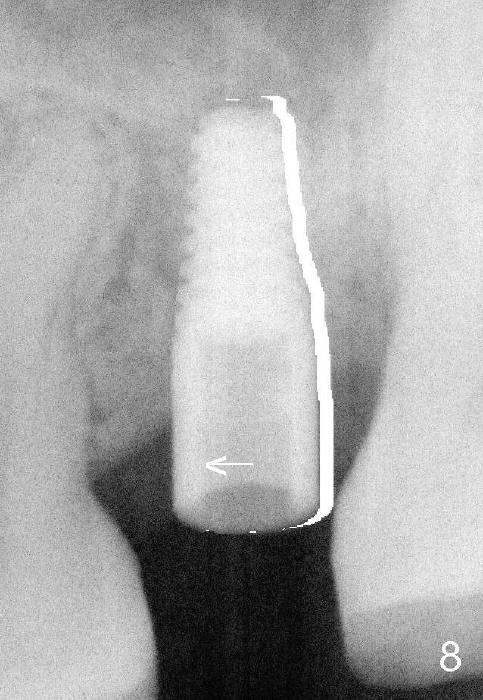

How to fix it? As soon as the deviation is noted, remove the drill/reamer/implant (Fig.6). Remove the resistant area with a Lindamann bur (Fig.7 red region). The implant should be able to be placed in a correct position (Fig.8).